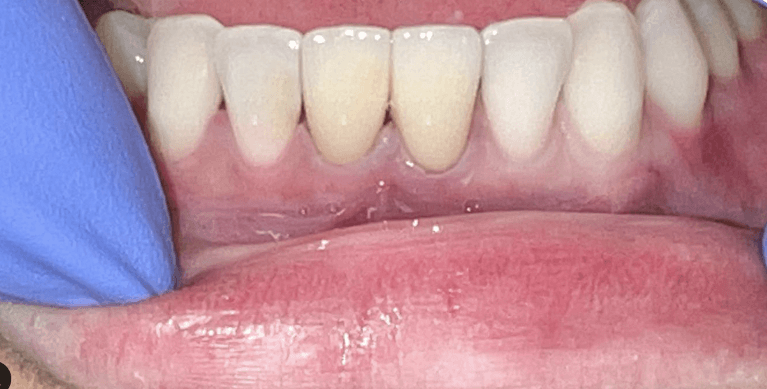

Laser gingivectomy(gum lift) to fix gummy smile and zoom whitening to lighten teeth color